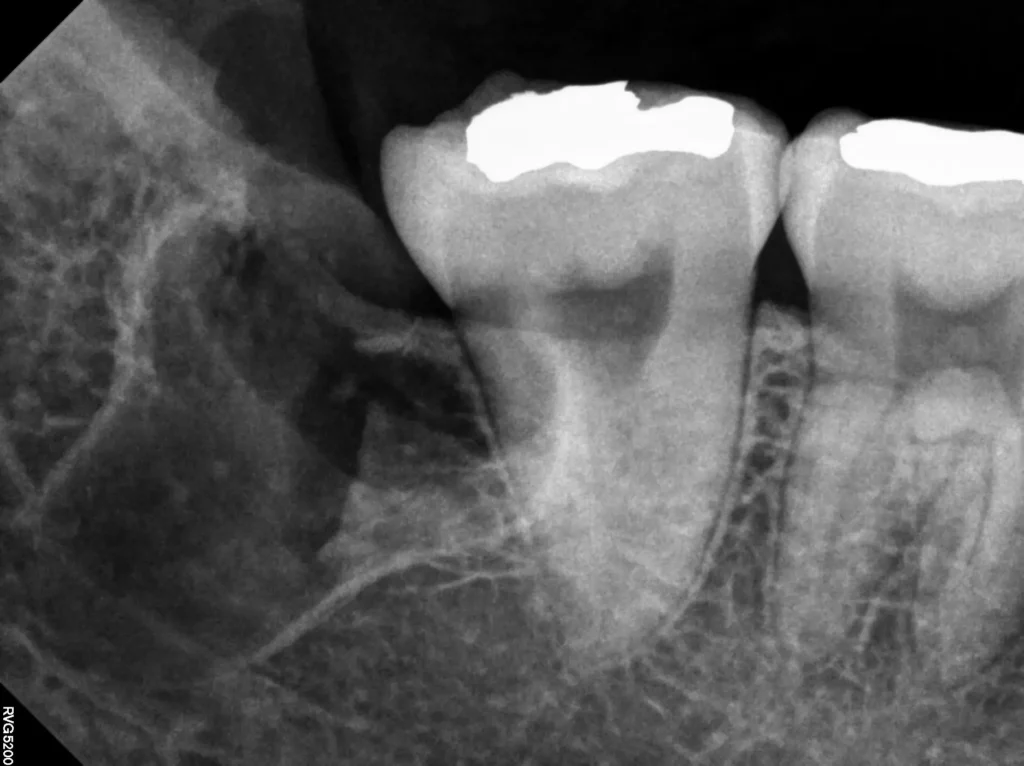

환자분께서는 왼쪽 아래 사랑니 부위가 붓고 통증이 심해 내원하셨습니다.

아픈 사랑니 (왼쪽 아래)

사랑니를 감싸고 있는 치아 낭이 잇몸 밖으로 살짝이라도 노출되면(개방), 잇몸과 치아 사이에 틈이 생깁니다. 이 틈으로 음식물과 세균이 들어가면 염증이 시작되는데, 이를 **치관주위염(Pericoronitis)**이라고 합니다.

- 초반에는 붓기가 가라앉기도 하지만, 세균 오염은 멈추지 않고 계속 진행됩니다.

- 처음 아프고 부었을 때 바로 발치하는 것이 가장 좋습니다.